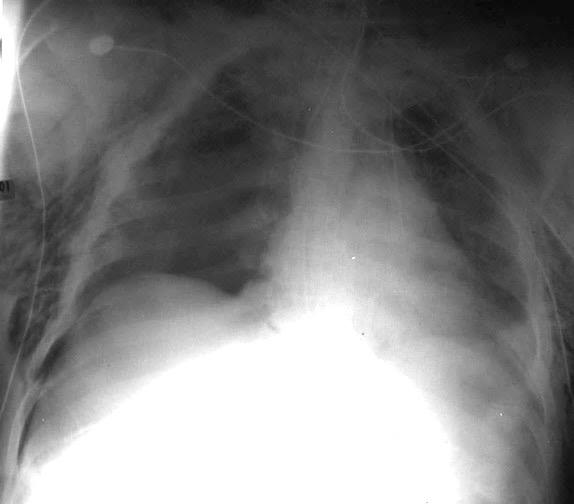

Empiema pleural izquierdo. Absceso del LID. Espondilodiscitis D11-D12.

Potsios C et al. Pyogenic Spondylodiscitis due to Streptococcus constellatus in an Immunocompromised Male Patient: A case Report and Review of the Literature. Case Reports in Infectious Diseases. 2019